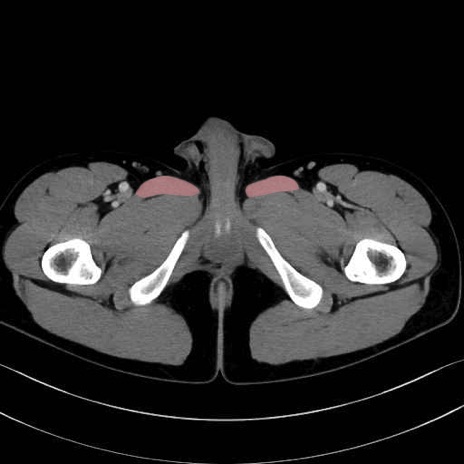

長内転筋(Adductor longus muscle)のCT画像の解剖

長内転筋 (Adductor longus)